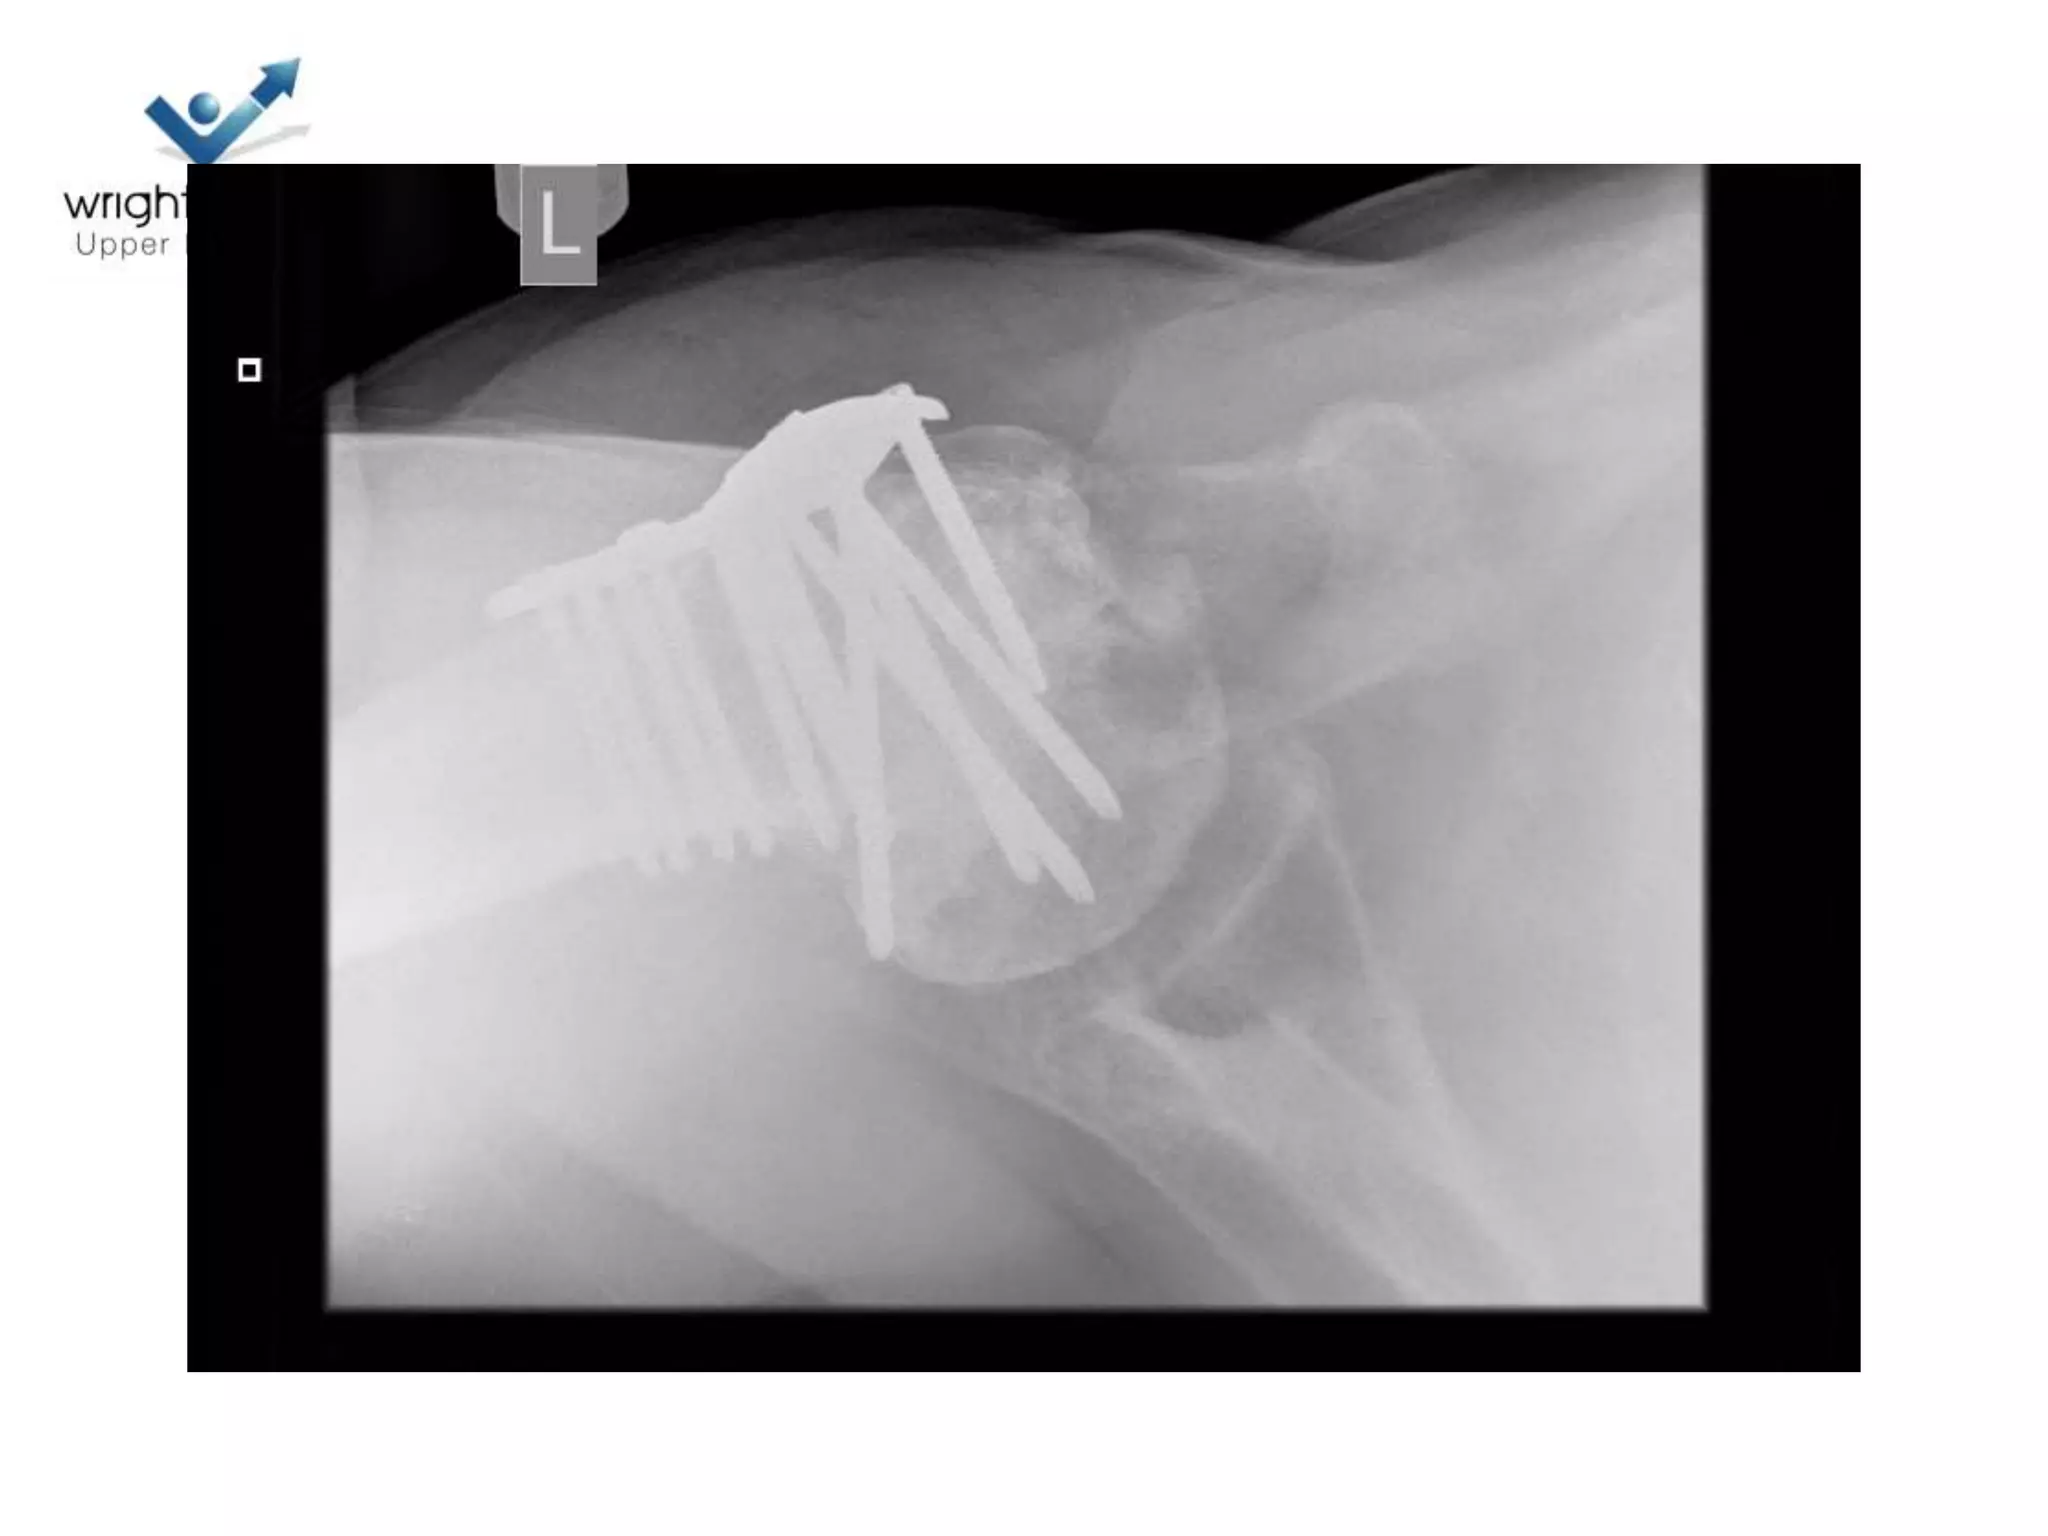

Hemiarthroplasty

• Getting it right

• Depth of prosthesis

• Version of prosthesis

• Size of the head